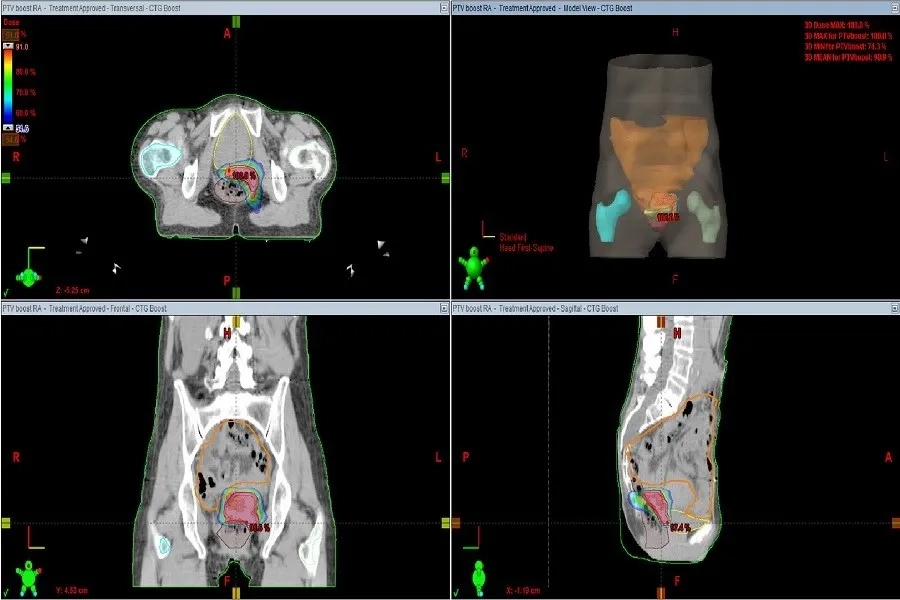

Xạ trị chiếu ngoài (EBRT) là phương pháp dùng máy chiếu tia bức xạ từ bên ngoài cơ thể vào cổ tử cung, hạch bạch huyết hoặc các cơ quan cần điều trị. Cách thực hiện tương tự chụp X-quang nhưng với liều tia mạnh hơn.

Trước khi chiếu, người bệnh sẽ được chụp CT để xác định chính xác vị trí. Mỗi lần chiếu chỉ vài phút, song việc căn chỉnh có thể mất đến 45 phút. Liệu pháp này hoàn toàn nhẹ nhàng và không gây đau.